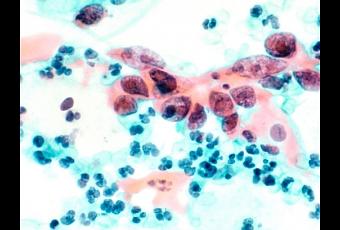

Alors que la couverture vaccinale contre le papillomavirus humain (HPV) reste très faible, aux alentours de 35% en France et aux Etats-Unis, cette conclusion du National Cancer Institute (NCI) américain est plutôt une bonne nouvelle. Un schéma de vaccination à dose unique pourrait suffire à générer des réponses immunitaires à long terme et assurer une protection satisfaisante contre les nouvelles infections à HPV et donc prévenir le cancer du col de l’utérus. Ces données, publiées dans la revue Cancer Prevention Research, sont indiscutables : 4 ans après la vaccination à 1 dose, 100% des femmes vaccinées présentent des anticorps contre les HPV 16 et 18.

La prise en compte clinique de ces nouvelles données pourrait, en la simplifiant, promouvoir cette vaccination anti-HPV et réduire non seulement l’incidence du cancer du col, mais aussi de certains autres cancers, comme les cancers de la gorge, le cancer anal ou encore des verrues génitales associées au HPV.